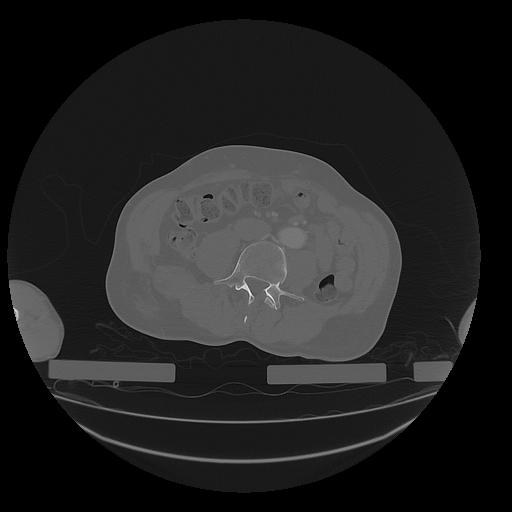

31 PULMON,CE,Vol,1.0,PULMON,,